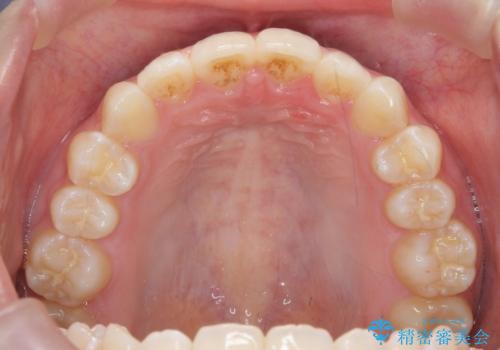

[ インビザラインライト ] 短期間で前歯だけを並べたい

担当医 大元洋佑